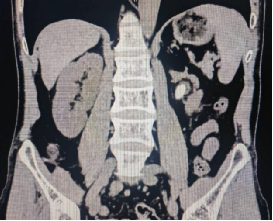

术前影像学检查: